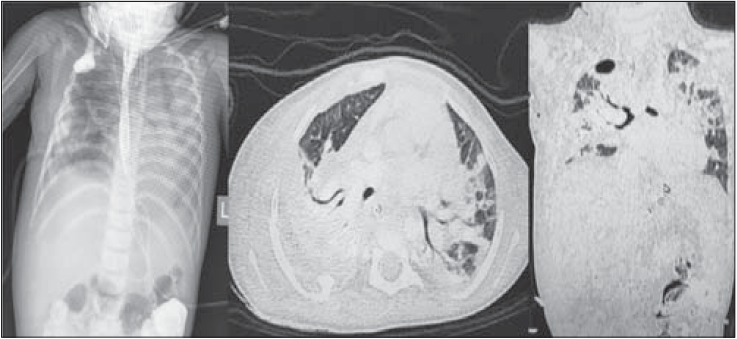

Проведено езофагографію: анастомоз спроможний. За результатами комп’ютерної томографії – двобічна плевропневмонія, двобічний гідроторакс, респіраторний дистрес-синдром (рис. 2).

Рис. 2. Результати комп’ютерної томографії органів грудної порожнини хворого